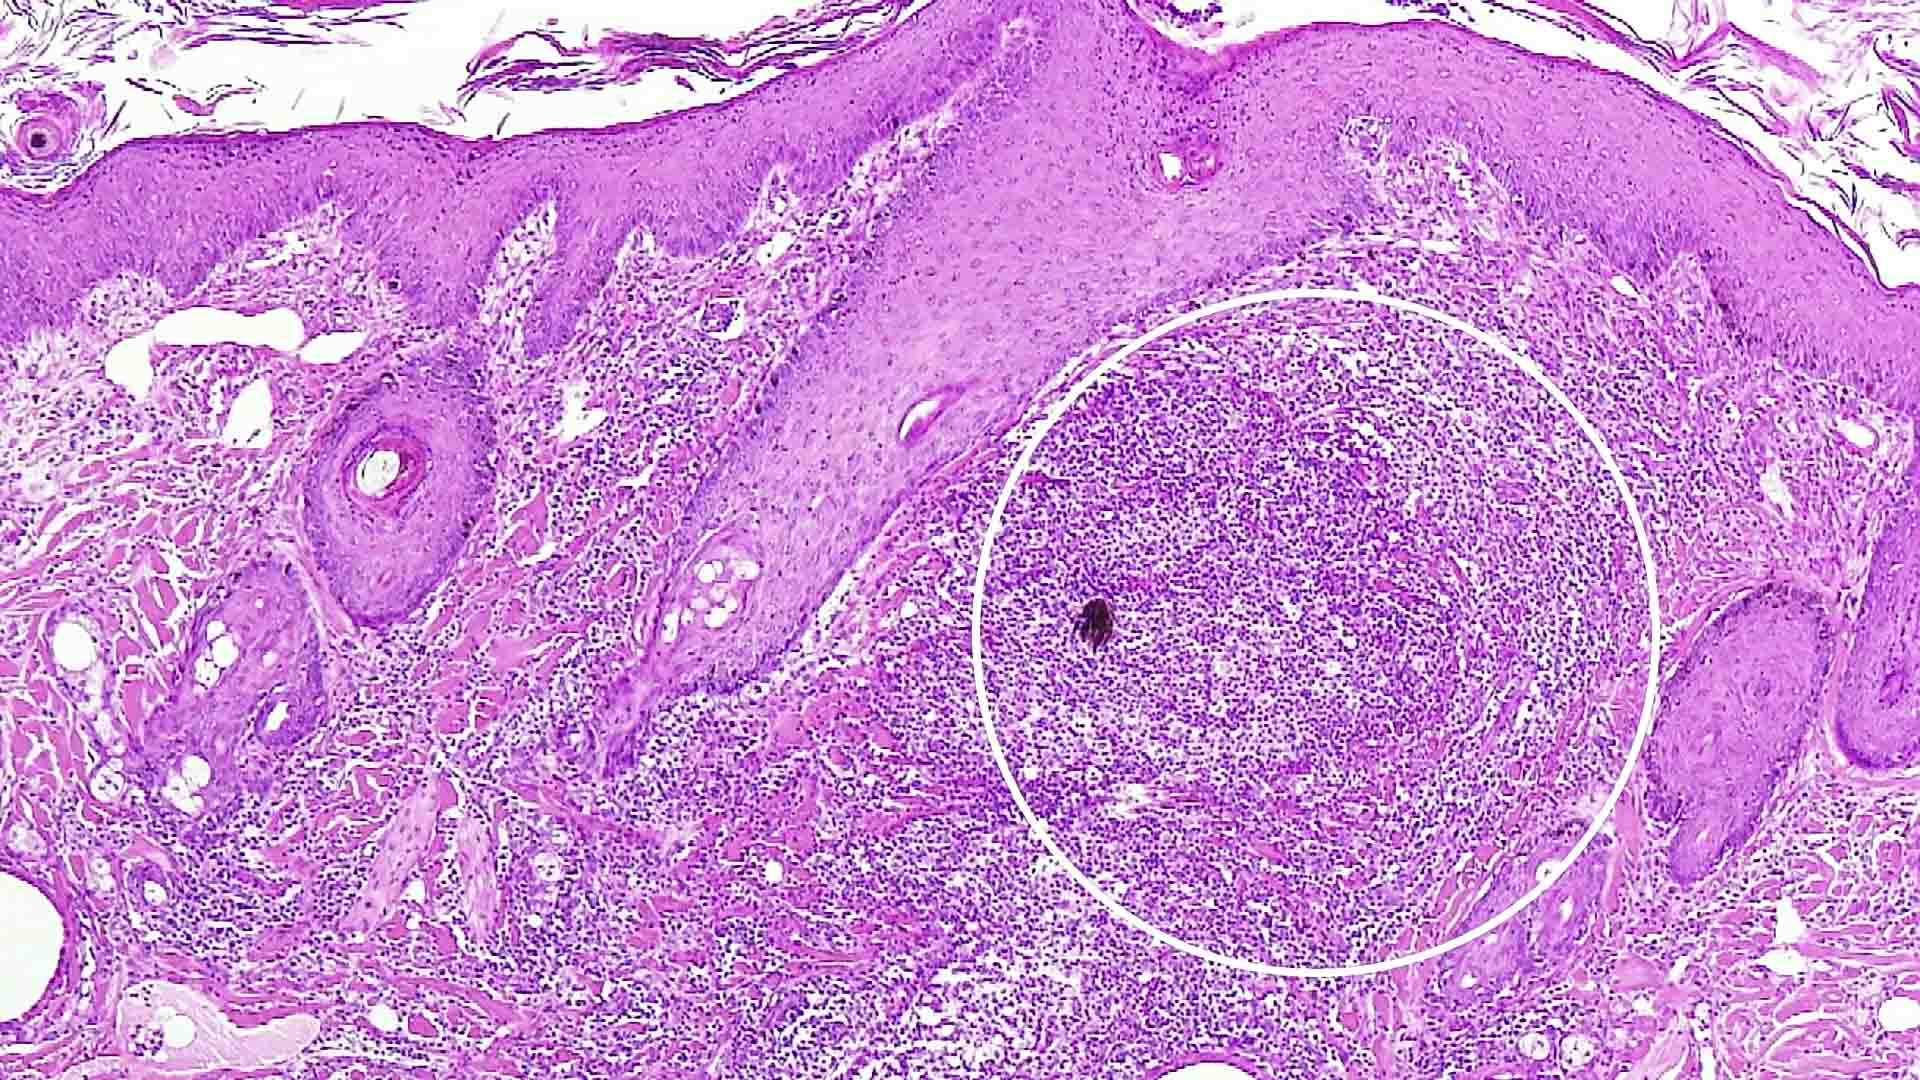

猫の希少・注目例に学ぶ!診断と治療の最前線〜好酸球性硬化性繊維増殖症〜

本映像では、猫の肺において「好酸球性硬化性繊維増殖症(Eosinophilic Sclerosing Fibroplasia)」の可能性が示唆された症例をご紹介します。Eosinophilic sclerosing lesionは、主にリンパ節や消化管での報告が多い中、肺に好酸球主体の硬化性病変を認めた本例は非常に稀であり、、、、